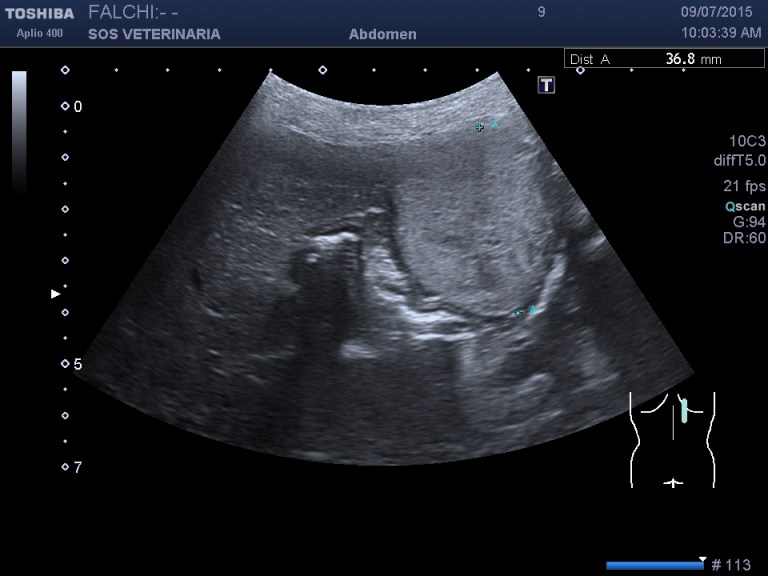

primo esame ecografico .volume surrenalico nei limiti,morfologia surrenalica rispettata , ,lesione focale epatica compatta omogenea nei settori di sx altre piu’ piccole lesioni focali meno demarcate e definite sempre nei settori di sx

ecografia di secondo livello con CEUS

fase arteriosa isoenanchement

fase portale e tardiva ipoenachemente

primo contraddittorio la ceus denuncia un circolo portale disorganizzato quindi una lesione significativa, maligna in prima ipotesi, era giusto fare un semplice agoaspirato? non era meglio fare una biopsia? rimanderei le conclusioni a dopo